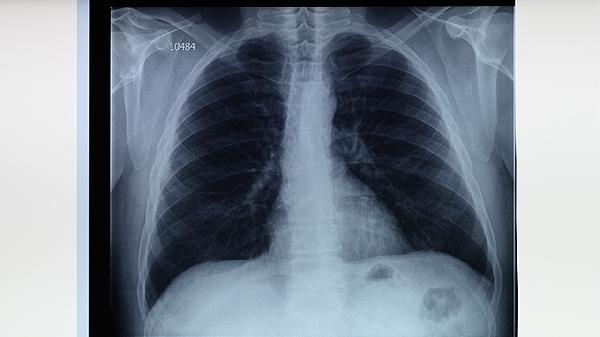

肺结核患者应在传染病专科医生指导下完成6-9个月的标准化疗方案,期间可配合中药调理。治疗期间需定期复查胸部影像学检查和痰菌检测,避免擅自停用抗结核药物。保持居室通风,保证高蛋白饮食与充足睡眠,咳嗽时注意掩住口鼻防止飞沫传播。